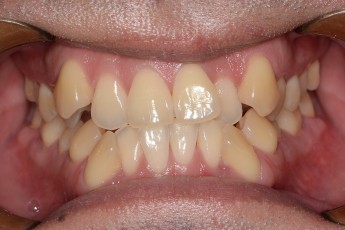

Before